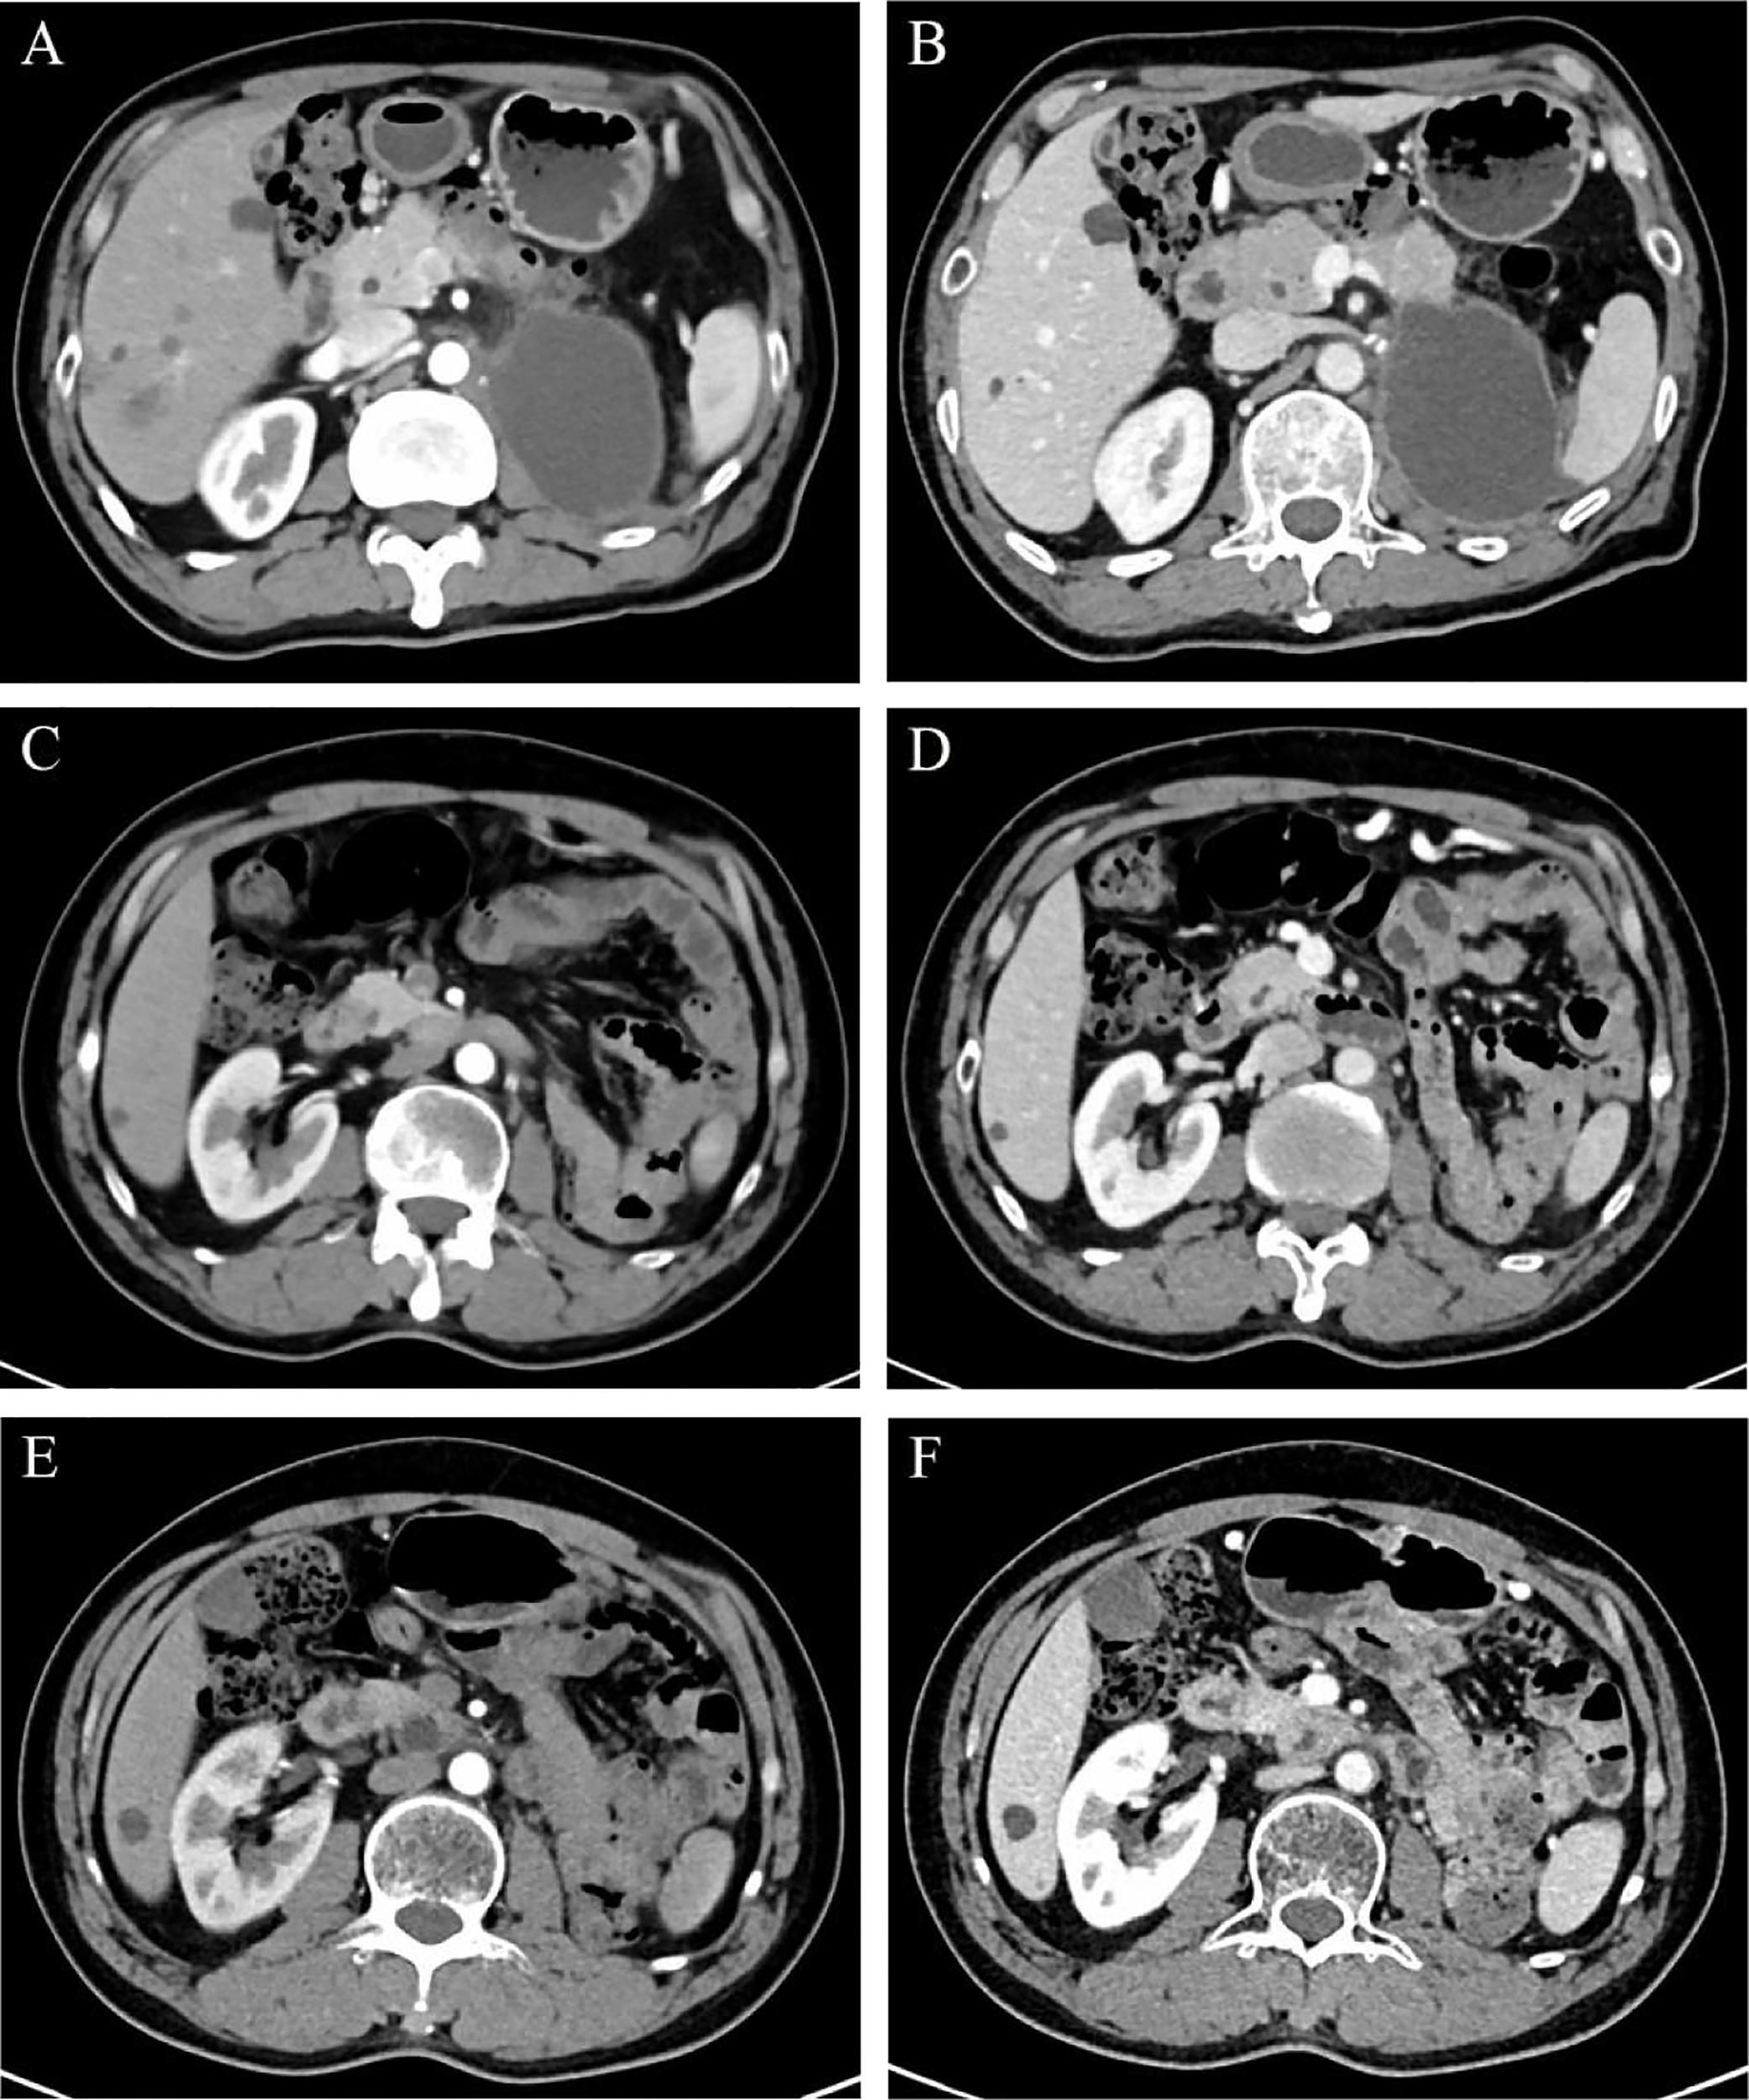

One month after the radical surgery, a dynamic contrast-enhanced CT scan revealed a cystic lesion in the original left kidney area measuring 8.0 × 5.7 cm in cross-section (Figures 4A, B). Multidisciplinary consultation suggested that the patient should be given salvage therapy. From July 2020 to May 2021, he received eight cycles of chemotherapy with the SOX (oxaliplatin plus S-1) regimen in the first cycle and then the XELOX (oxaliplatin plus capecitabine) regimen in cycles 2-8 due to a general rash during oral S-1. After completion of chemotherapy, he was then subjected to 28 local radiotherapies at the original left renal area delivered by volumetric modulated arc therapy (VMAT) with a total dose of 5600 cGy in 200 cGy per fraction.

Regular dynamic contrast-enhanced CT scan manifestations in CMP (A, C, E) and NP (B, D, F). (A, B on July 24, 2020) An 8.0 × 5.7 cm cystic low-density lesion was found in the original left renal area. (C, D on August 2, 2021) The cystic effusion was absorbed completely. (E, F on August 17, 2022) The original left kidney area was filled with intestines. Abbreviations: CMP, corticomedullary phase; NP, nephrographic phase.

Periodic dynamic contrast-enhanced CT scans showed a gradual reduction in the cystic lesion in the left renal region, and a re-examination on August 2, 2021, showed that the lesions had disappeared (Figures 4C, D). Until this report, the patient remained stable with outpatient follow-up for 30 months and no evidence of recurrence (Figures 4E, F). The levels of the tumor markers gradually decreased after subsequent treatments during follow-up (eFigure 3). The timeline of interventions and outcomes for the patient is presented in eFigure 4.